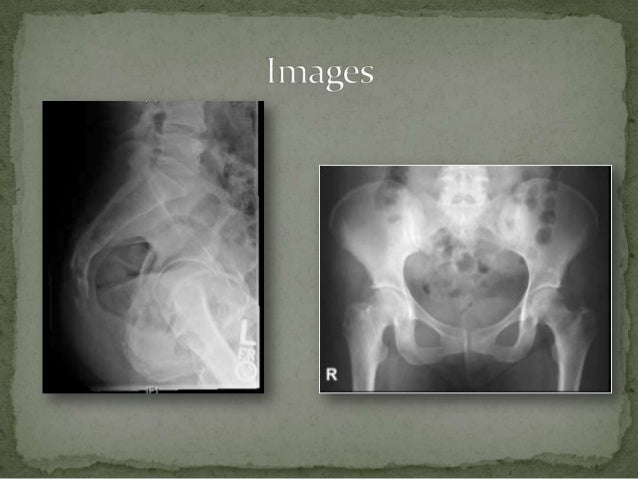

The coccyx lateral view is used to show the most distal region of the spine in a lateral position. This can dramatically decrease the amount of radiation delivered to the patient and can especially decrease the amount of radiation delivered to. Correct coccyx and central ray alignment demonstrate coccyx free of superimposition and projected superior to pubis. This observation has been common to all roentgenologists for many years and does not. In coccygodynia, pain is most severe in the sitting position.

The coccyx lateral view is used to show the most distal region of the spine in a lateral position. It is used to show sacrum and coccyx anatomy, and to investigate the cause of sacral and coccyx pain in both acute and chronic conditions. Align long axis of coccyx to cr and to midline of table/grid; Place a support under waist and between knees and ankkles to maintain patient position and ensure comfort. Cushion for patients head ;

Ensure no rotation of body and pelvis for true lateral position. This prompted a study comparing lateral roentgenograms of the coccyx taken with the patient lying on the side. The coccyx lateral view is used to show the most distal region of the spine in a lateral position. • patient position—supine position • part position • align midsagittal plane to cr and midline of table and/or ir. This can dramatically decrease the amount of radiation delivered to the patient and can especially decrease the amount of radiation delivered to.